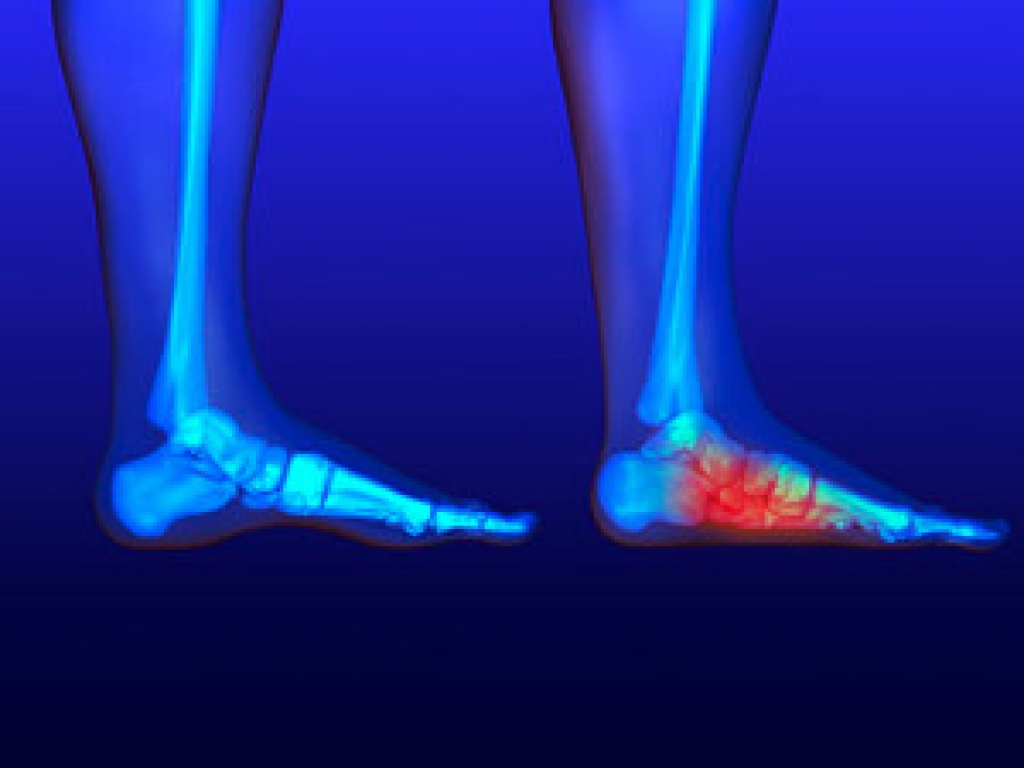

Foot Pain

Foot pain is a very broad condition that could be caused by one or more ailments. The most common include:

To figure out the cause of foot pain, podiatrists utilize several different methods. This can range from simple visual inspections and sensation tests to X-rays and MRI scans. Prior medical history, family medical history, and any recent physical traumatic events will all be taken into consideration for a proper diagnosis.